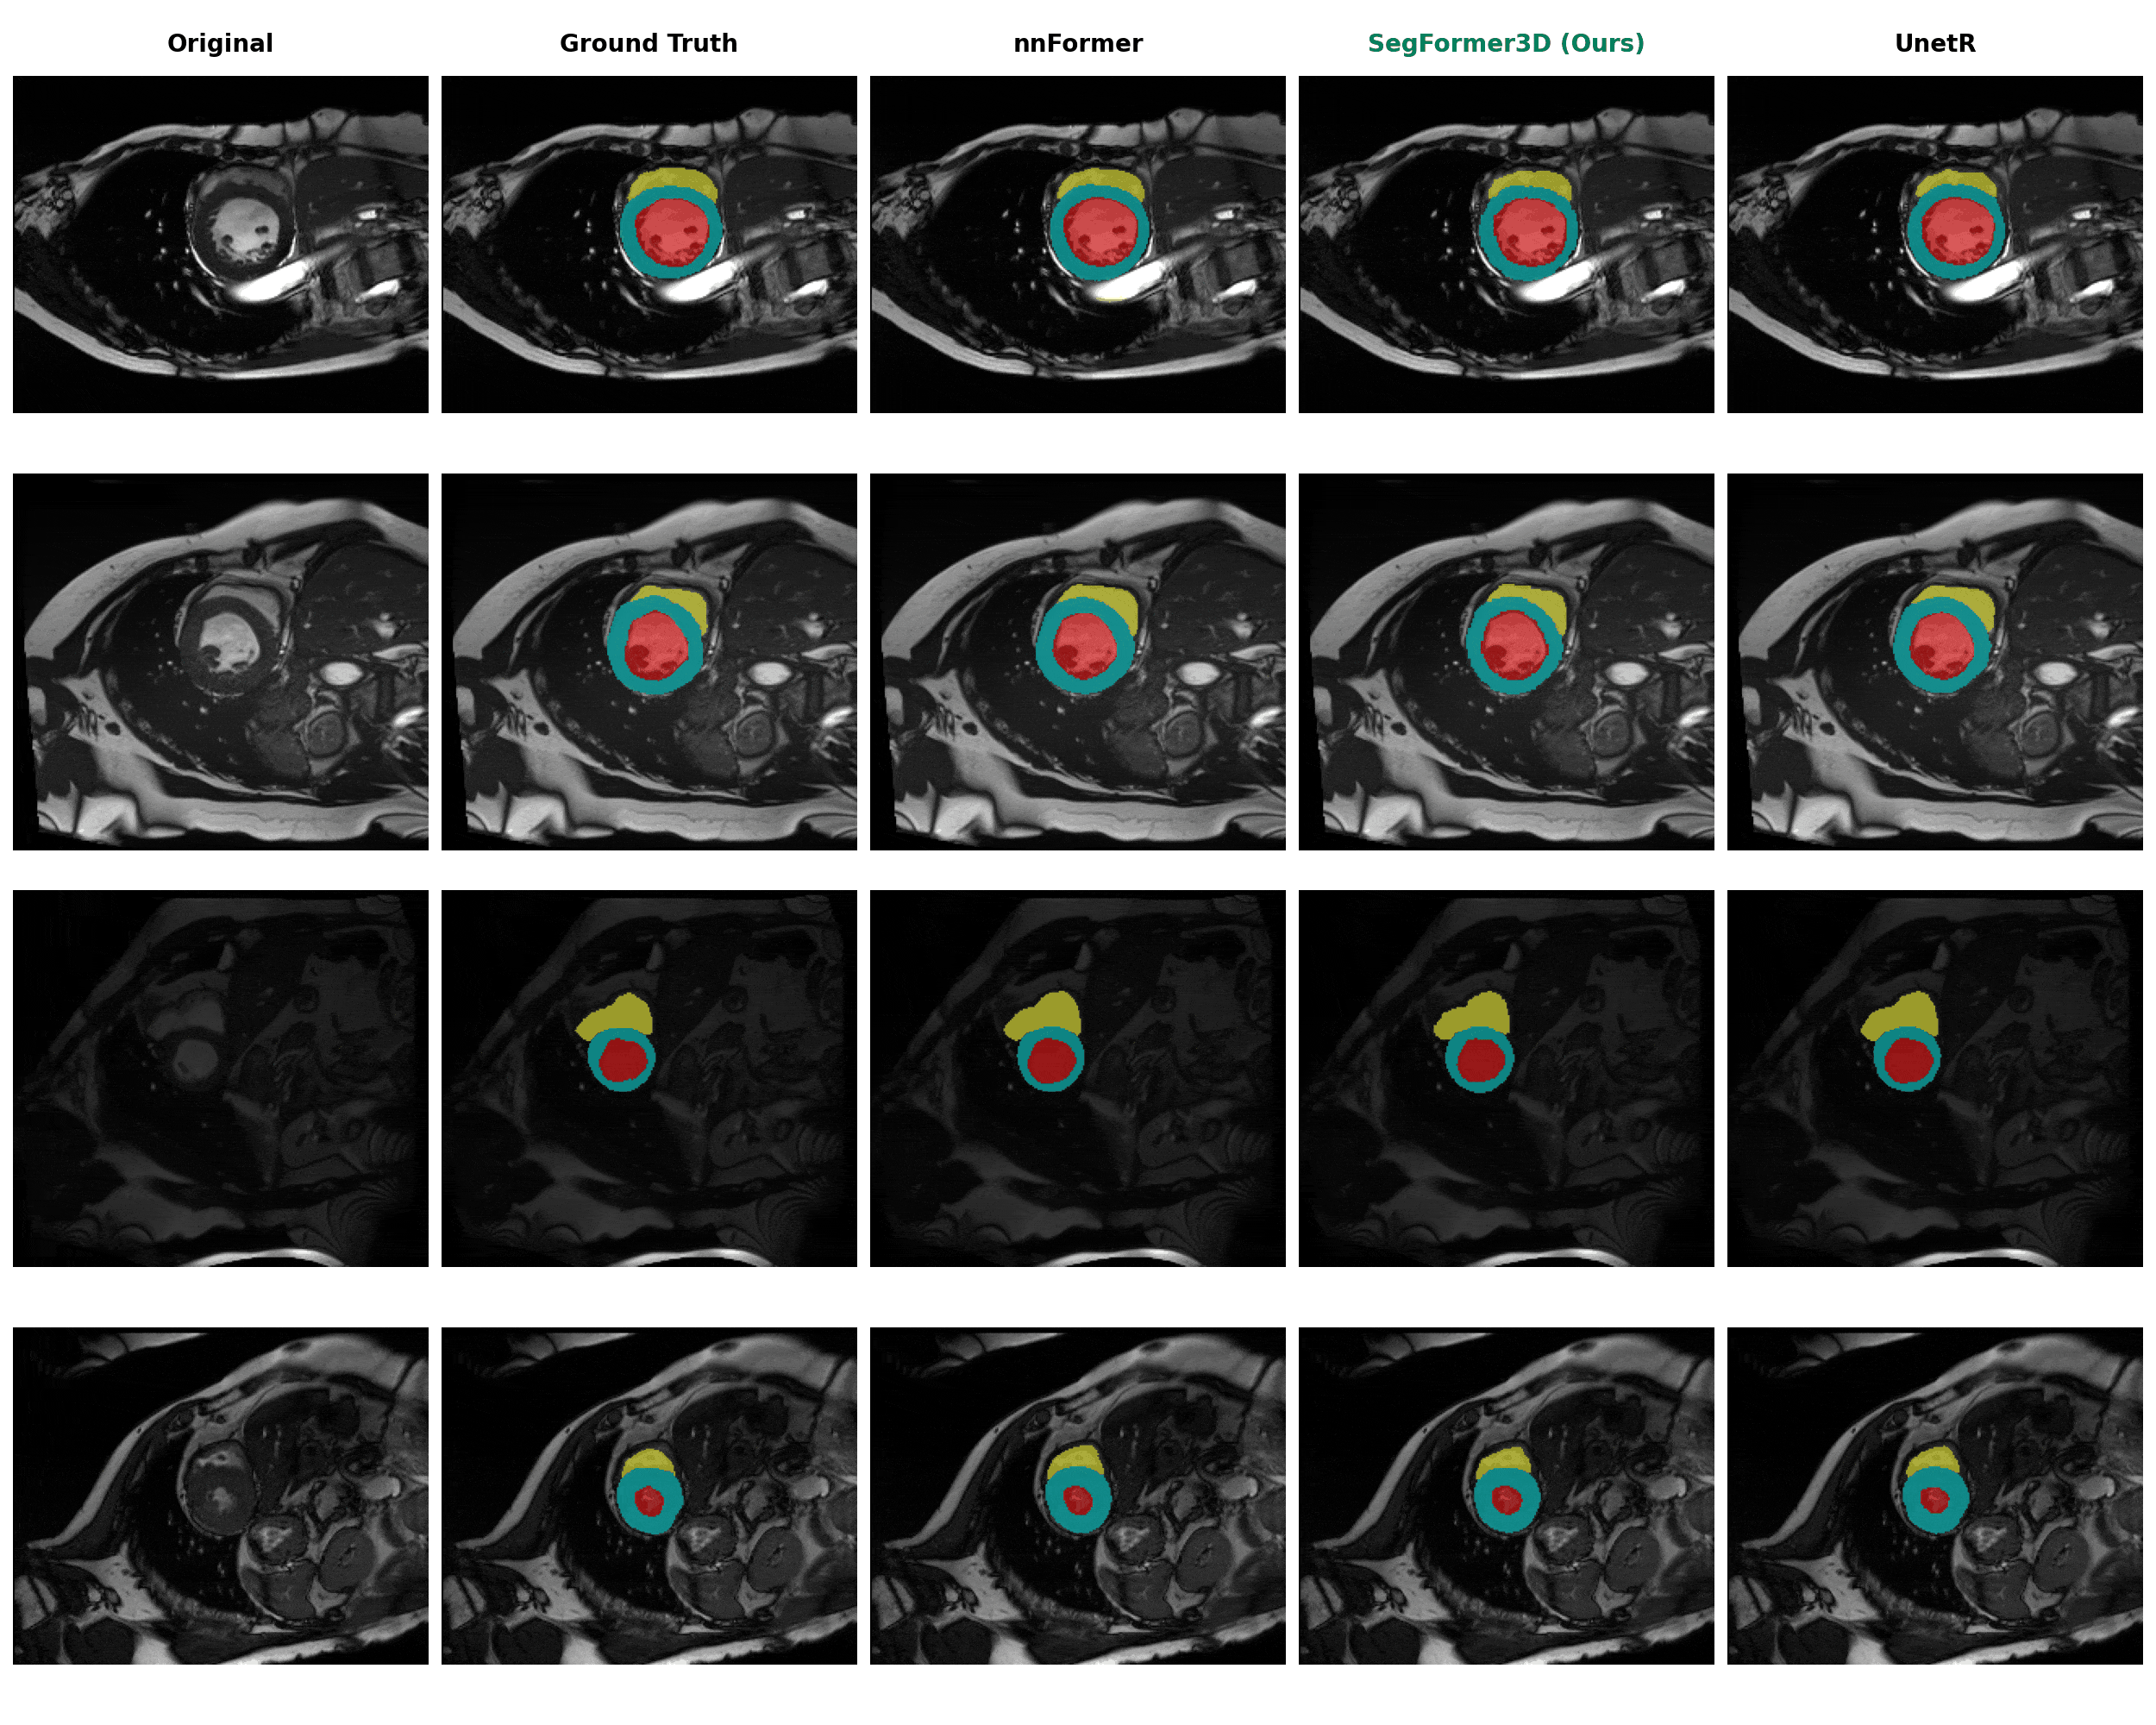

Qualitative Results

We compare SegFormer3D (highlighted in green) against state-of-the-art baselines on three medical imaging datasets. Despite being significantly lighter, our model produces highly accurate segmentation masks across all datasets.

Automated Cardiac Diagnosis (ACDC)

Segmentation of cardiac structures: Right Ventricle (RV), Myocardium (Myo), and Left Ventricle (LV).

ACDC Segmentation Results